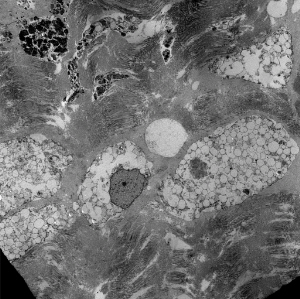

Immunohistochemistry and ultrastructural findings

- immunohistochemistry for lysosomal storage disorders not well developed

- ultrastructural findings useful in diagnosis

- lysosomal vacuoles with ill-defined contents

- may see glycogen granules

Lysosomal vacuoles in mucolipidosis (skin biopsy)